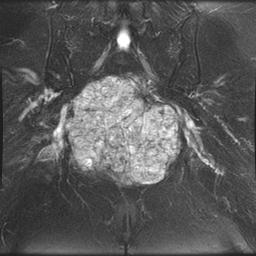

Gross

- lobulated bluish / gray

- extensive gelatinous translucent areas which are focally cystic & haemorrhagic